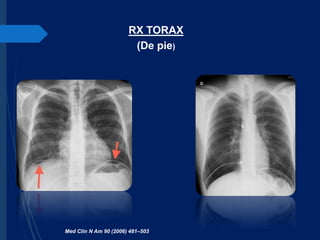

RX TORAX

(De pie)